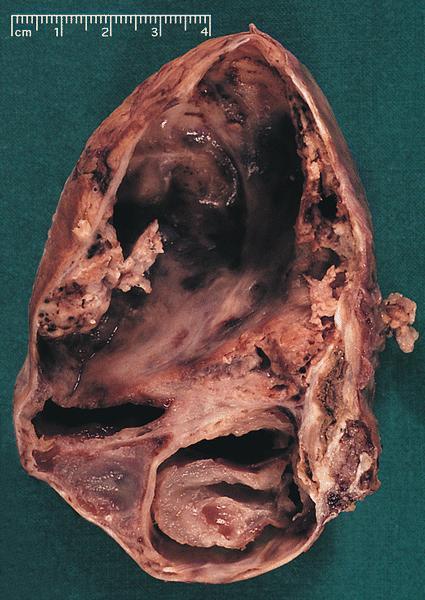

Gross description

- Range from 0.5 to 34.5 cm, with a mean diameter of 6 cm

- Well defined, encapsulated, with variable amount of solid and cystic patterns

- Smaller lesions tend to be more solid but less sharply circumscribed

- Larger tumors demonstrate a fibrous pseudocapsule and have a variegated and friable cut surface

- Cystic degeneration and hemorrhage are common findings in larger specimens

- Rarely, may extend into adjacent structures, such as duodenum

- Reference: Arch Pathol Lab Med 2020;144:829

Gross images

Contributed by Omid Savari, M.D., Dr. Andreas Schulz, Manfred Stolte, M.D., Dr. Helmut Luchtrath, Wei Chen, M.D., Ph.D., Nakul Anush Ravish, M.B.B.S. and Case #121